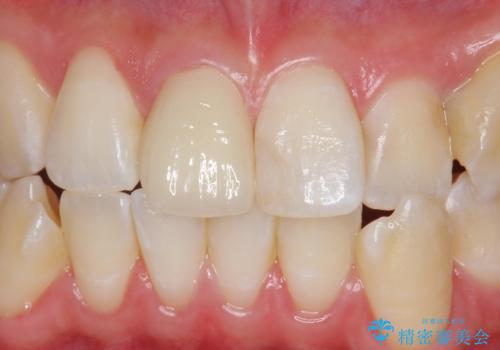

前歯の色が気になる。オールセラミッククラウンでのやり替え

色・形ともに改善され、大変喜んでいただけました。

- 前歯のかぶせ物の色が気になるとのことで来院された患者様です。

セラミッククラウンで作り変えていきます。